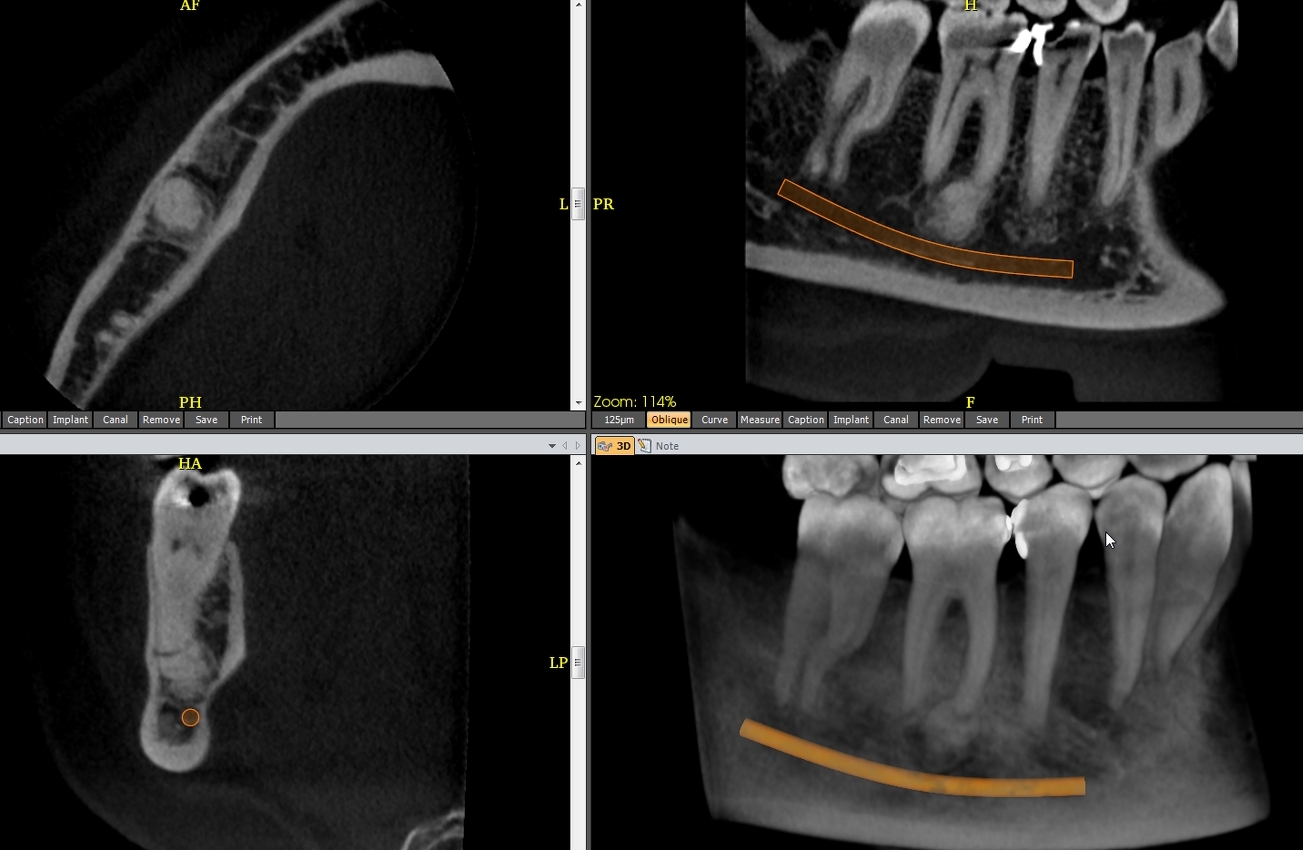

CBCT :

A. Observez sur les reconstructions axiale et panoramique les lésions apicales de :

a.46

b.43

c.et du bloc incisif.

A. Les dysplasies osseuses (ou cémento-osseuses) focale et périapicale, (Fig.1 à 3), (anciennement cémentome) sont les plus fréquentes lésions fibro-osseuses périapicales non néoplasiques ; proches du fibrome cémento-ossifiant, beaucoup plus rare et dont on a parfois du mal à la distinguer. De découverte le plus souvent radiologique, chez une femme d’âge moyen, le plus souvent à la mandibule :

– elles évoluent toujours sur dent vivante, en trois stades :

> stade I : dit « ostéolytique », lacune apicale, correspondant à du tissu fibreux, sur dent saine (Fig.1) ;

> stade II : intermédiaire, un dépôt de cément se formant au sein de la clarté apicale (Fig.2) ;

> stade III : hyperdensité apicale cernée par liseré clair périphérique (Fig.3)

B. La dysplasie osseuse (ou cémento-osseuse) floride (Fig.4). Elle touche surtout la femme noire d’âge moyen, affectant les deux maxillaires de façon plus ou moins diffuse et symétrique, associant des lésions de grande taille à tous les stades, pouvant s’infecter et se compliquer d’ostéite.